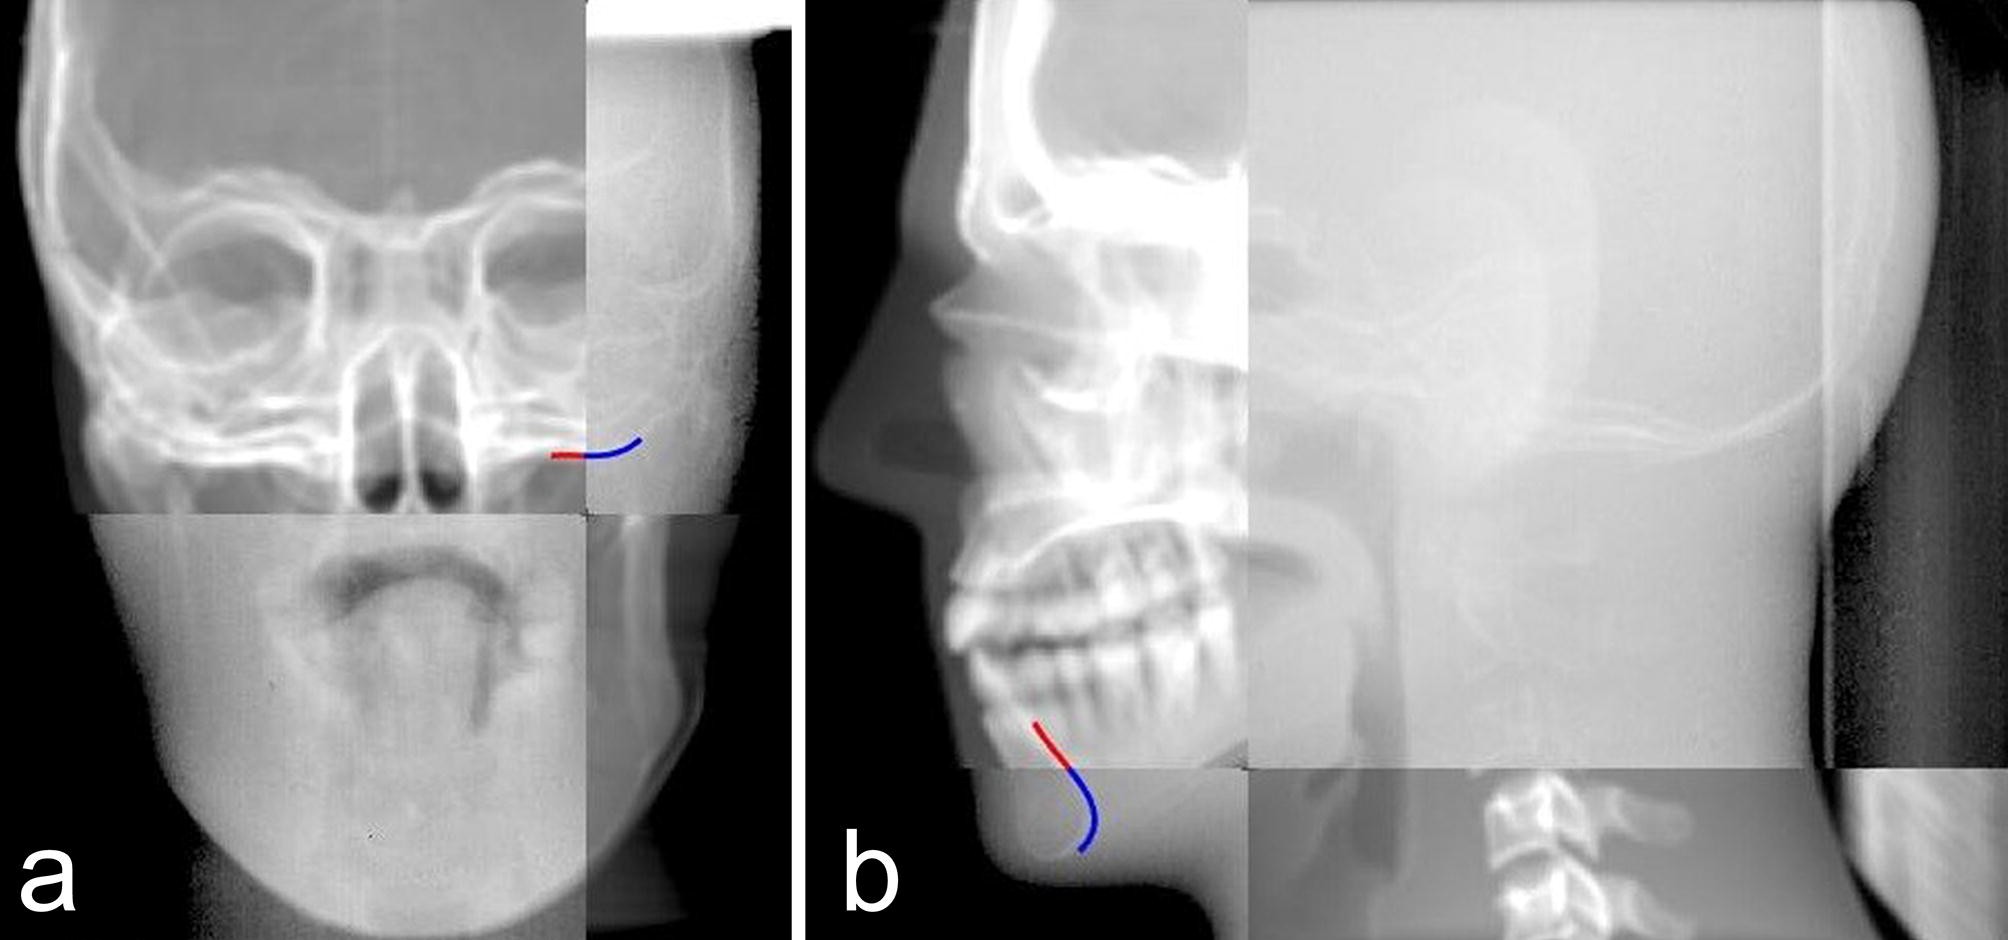

Figure 2

Figures of the registration result of the new registration. (a) Results of anteroposterior registration, (b) results of lateral registration.